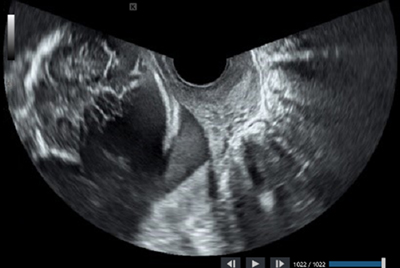

「SONOVISTA LX」は,コニカミノルタが2019年に発売した「SONOVISTA GX30」に続く,経膣⽤超⾳波診断装置。エレガントでスタイリッシュなデザインを有し,省スペース設計と優れた操作性を継承しつつ,新技術の搭載によりさらなる⾼画質化を実現した。診断の精度向上を⽀援するとともに,広視野⾓による効率的な検査で患者の負担軽減に貢献する。

「SONOVISTA LX」には,コニカミノルタ独⾃の⾼画質化技術「Dual Sonic」を進化させた新技術「Dual Sonic Advance」を搭載している。

「Dual Sonic」とは,送信開⼝を中⼼部と辺縁部に2分割し,中⼼部は⽣体内の浅部と深部の双⽅に有効な広帯域送信波,辺縁部は深部に有効な低周波送信波を形成し,最適な超⾳波ビームを制御することで浅部から深部まで全体に渡ってノイズの少ない超⾳波画像を得ることができるようにする技術で,2021年に⽇本超⾳波医学会の第21回技術賞を受賞した。「Dual Sonic Advance」は,「Dual Sonic」の2分割送信を多分割送信に進化させ,さらに精密に超⾳波ビームを制御することで,より均⼀性が⾼く,⾼精細な画像描出を可能にしている。この新技術により,⼦宮や胎児を⾼画質で明瞭に描出し,診断や検査の精度向上を⽀援する。

また,従来から広視野⾓として⾼い評価を得ている経腟プローブの視野⾓220度表⽰を継承しており,広範囲を⼀度に確認できるため効率的な診断・検査が可能で,患者の負担軽減に貢献する。